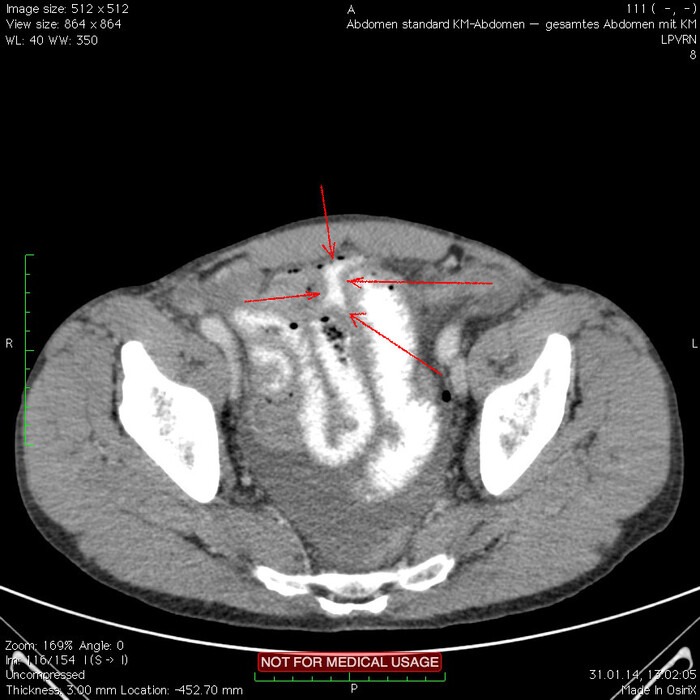

Отмечаем про себя, что в верхних квадрантах свободного газа не так уж и много. При перфорации желудка газа намного больше. Также выясняем, что газ есть также и в нижних квадрантах:

Ещё бросается в глаза массивный выпот (стрелки) во всех этажах, а также утолщение брюшины на всём протяжении, что указывает на диффузный (разлитой) перитонит. Тут, кстати, уже мягкотканное окно:

Итак, имеет место быть свободный газ в брюшной полости + свободная жидкость + перитонит. Определённо перфорация! Осталось найти источник. Желудок не подходит по механизму, а точнее по локализации травмы. Мочевой пузырь - в нём нет воздуха. Остаётся методом исключения только кишечник. Толстый или тонкий? Явно не верхние отделы толстого кишечника (ободочная кишка в области печеночного и селезеночного углов, а также поперечная исключаются - было бы больше воздуха). Сигма и нисходящая тоже заполнены стулом и воздухом. Получается, что тонкий кишечник всему виной.

Верхние (проксимальные) отделы точно не причём. Жидкость (звёздочки) больше в малом тазу, тут же и воздух. Для сравнения верхний этаж:

Hижний этаж:

И тут СТОП! А это чтo такое???

Кишке это точно не принадлежит, как ни крути. Это вышедший за пределы кишки контраст, который пациент выпил!

Осталось только место выхода найти:

Итого: перфорация тощей кишки в дистальных отделах, разлитой перитонит.

Был успешно прооперирован, место перфорации ушито, выписан.